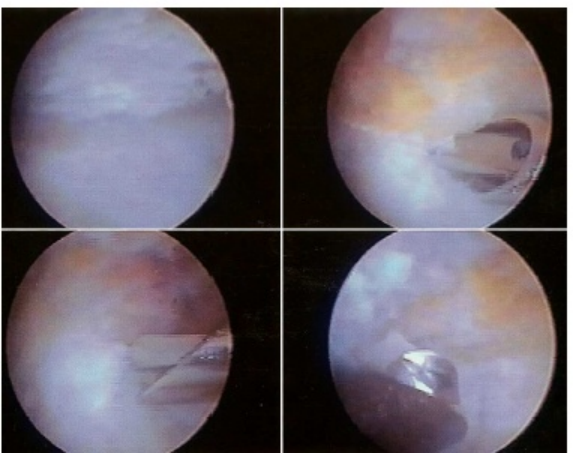

关节镜下关节清理手术

手术治疗的目的在于尽量重建关节,以消除疼痛、改善关节活动度,现有手术方式,关节清理术、关节成形术、跖骨背侧楔形截骨术、硅胶人工关节置换术。

对于中晚期患者大部分学者主张早期手术干预,手术方法主要有第二跖骨背侧楔形截骨术、关节滑膜清理术、关节成形术、关节置换术等。